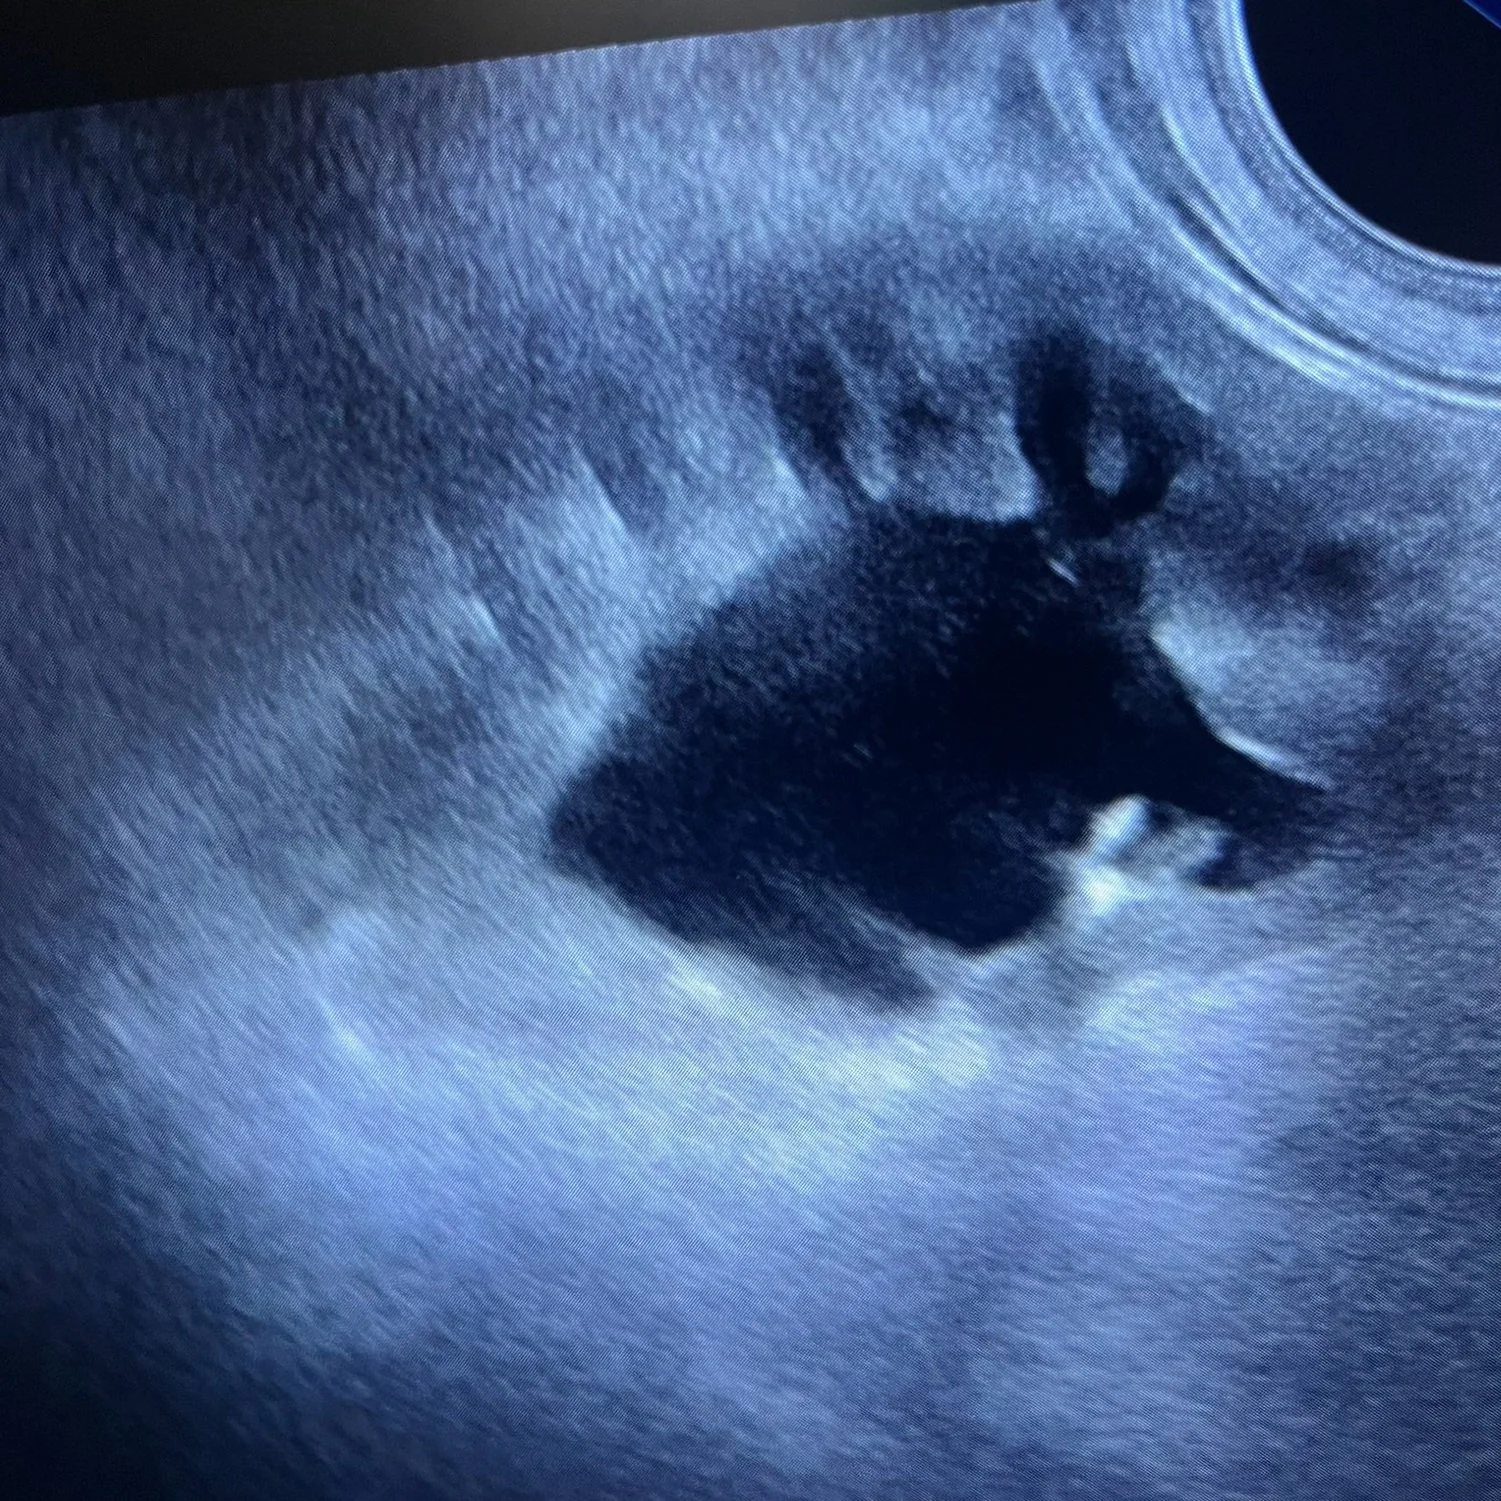

During a veterinary ultrasound, we use a small handheld probe that glides smoothly over your pet's fur and skin. The probe emits sound waves that bounce off internal organs, allowing us to create live, detailed images of your pet's internal structures on a monitor. This allows us to examine the abdomen, heart, or other areas with precision, capturing important information without causing any discomfort to your pet.